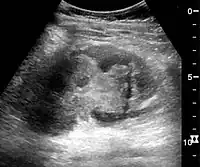

In medical imaging, the acute changes in the kidney are often examined with renal ultrasonography as the first-line modality, where CT scan and magnetic resonance imaging (MRI) are used for the follow-up examinations and when US fails to demonstrate abnormalities. In evaluation of the acute changes in the kidney, the echogenicity of the renal structures, the delineation of the kidney, the renal vascularity, kidney size and focal abnormalities are observed.[16] CT is preferred in renal traumas, but US is used for follow-up, especially in the patients suspected for the formation of urinomas. A CT scan of the abdomen will also demonstrate bladder distension or hydronephrosis.

Renal ultrasonograph of acute pyelonephritis with increased cortical echogenicity and blurred delineation of the upper pole.[16]